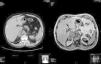

The patient is a 48-year-old male. During a CT study for pulmonary emphysema, a nonspecific nodular lesion was observed in the right adrenal gland, measuring 4×2.5×2cm. To complete the study of the incidental adrenal mass, an MRI was ordered, which showed evidence of a heterogenous right adrenal mass measuring 6.8×4.4×3.9cm that was in close contact with the pillar of the diaphragm and the inferior vena cava, which was being compressed (Fig. 1). These findings were compatible with carcinoma or a metastatic lesion. At the time of the MRI, the patient expressed the appearance of constant, mild pain in the right hypochondrium.

Rapid growth is characteristic, as observed in this case (Fig. 1), and lesions smaller than 5cm are usually asymptomatic. The most frequent symptoms are abdominal and lumbar pain, the sensation of a mass effect in the hypochondrium, as well as asthenia and weight loss.10 Almost all the published cases with lesions larger than 8cm presented distant metastasis at the time of diagnosis.1,3,10